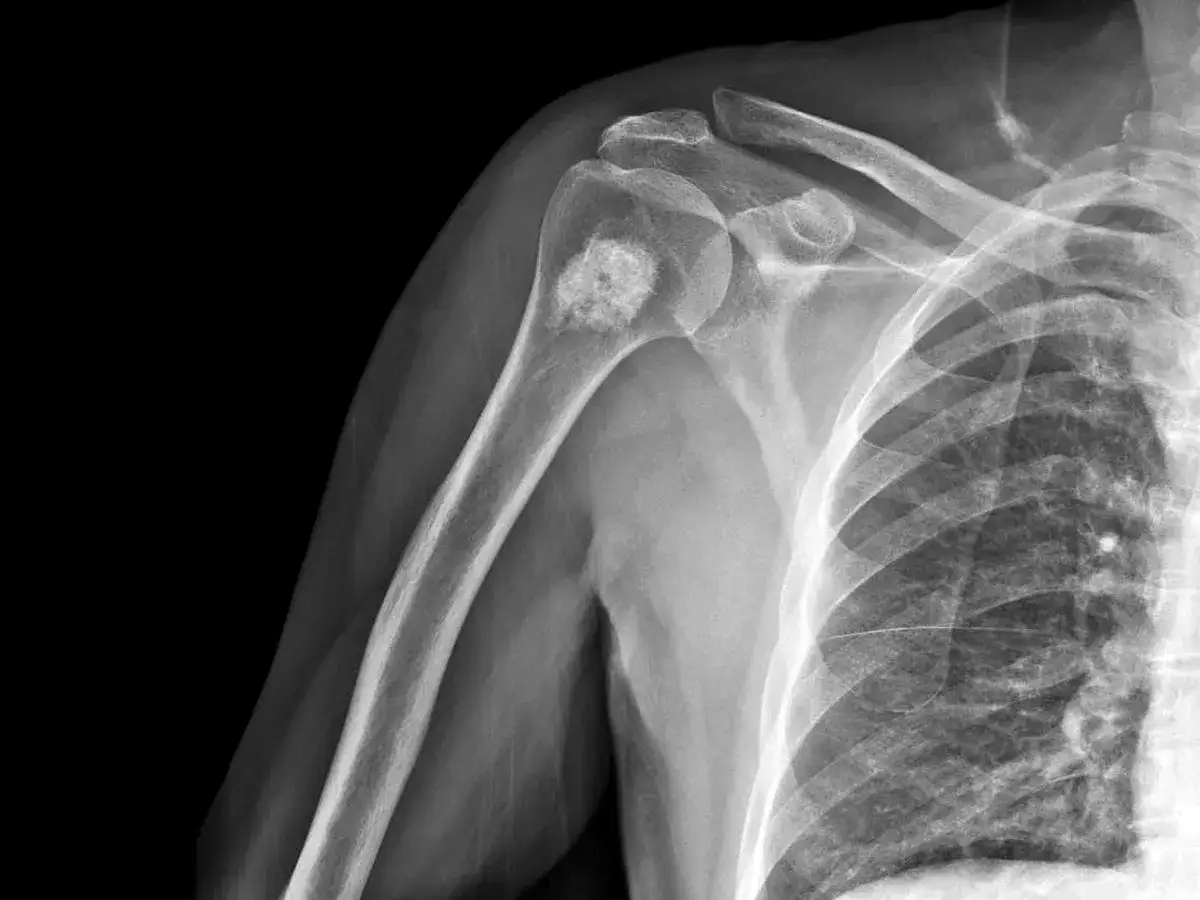

Obrzęk i wyczuwalne guzy: Lokalne zmiany, których nie wolno ignorować

W niektórych przypadkach, zwłaszcza gdy przerzuty są duże lub zlokalizowane w łatwo dostępnych miejscach (np. kości długie, żebra), mogą być widoczne lub wyczuwalne miejscowe obrzęki lub nawet guzy. Tego typu zmiany, które pojawiają się bez wcześniejszego urazu i nie ustępują, zawsze wymagają pilnej konsultacji lekarskiej i dalszej diagnostyki obrazowej. To sygnał, że proces chorobowy postępuje i wymaga uwagi.

- Kości udowe i kości ramienne: W tych długich kościach również często pojawiają się zmiany.